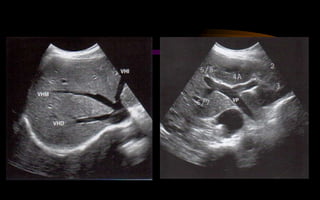

ANATOMIA DE

COUINAUD

 Se utiliza para localizar

una lesión hepática

 Se basa en segmentos

portales y tiene

importancia funcional y

patológica.

 Cada segmento tiene un

aporte sanguíneo

(arterial, venoso portal y

venoso hepático),

linfáticos y drenaje biliar

propios

 Existen ocho segmentos

 Las venas hepáticas,

derecha, media e

izquierda dividen al

hígado longitudinalmente

en cuatro secciones